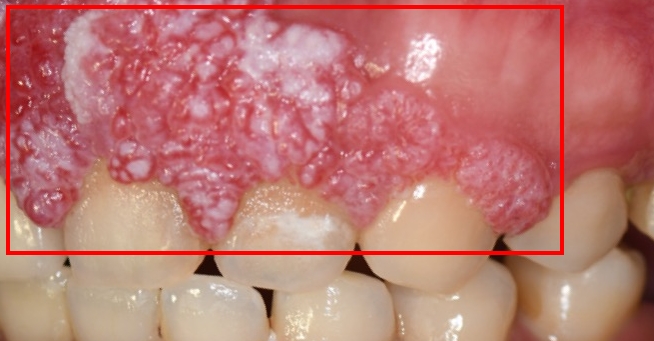

圖:許小姐腫瘤位於上顎齒齦區域

圖:許小姐腫瘤位於上顎齒齦區域手術當日,由中山附醫口腔顎面外科 邱昱瑋、陳怡孜及陳珮吟三位主治醫師組成的醫療團隊主導,採用電腦數位模擬與導航輔助手術。團隊先依模擬結果精準切除腫瘤,再依規劃完成牙齒重建位置,並將植體植入顴骨內,同時結合切割導版與電腦導航系統輔助。所有手術程序於同一日一次完成,包括 上顎口腔癌腫瘤切除、頸部淋巴清除、顴骨植牙與游離皮瓣重建,不僅大幅縮短整體治療時程,也有效降低患者身體與心理負擔。術後,許小姐已成功恢復正常咀嚼功能,生活品質明顯提升。